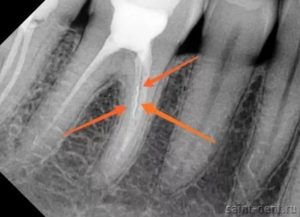

Итак, в этом случае мы видим на снимке «спиральку» в одном из каналов… Она показана стрелкой. Точками обведен воспалительный очаг вокруг корня зуба.

Чтобы хорошо очистить корневые каналы, стояла задача удалить этот отломок. При этом он находился довольно глубоко и имел небольшие размеры. Без вооруженного микроскопом глаза задача была бы трудновыполнимой. На фото ниже красной стрелкой показан отломок в глубине канала. Видя его, стоматологу уже намного легче обломок убрать и вывести наружу (зеленая стрелка).

В конечном счете инструмент был удален, а каналы полностью очищены и запломбированы.

Теперь нет сомнений, что гранулема, выросшая на корне зуба и грозившая его удалением, уйдет через несколько месяцев. И существованию зуба более ничего не будет угрожать.